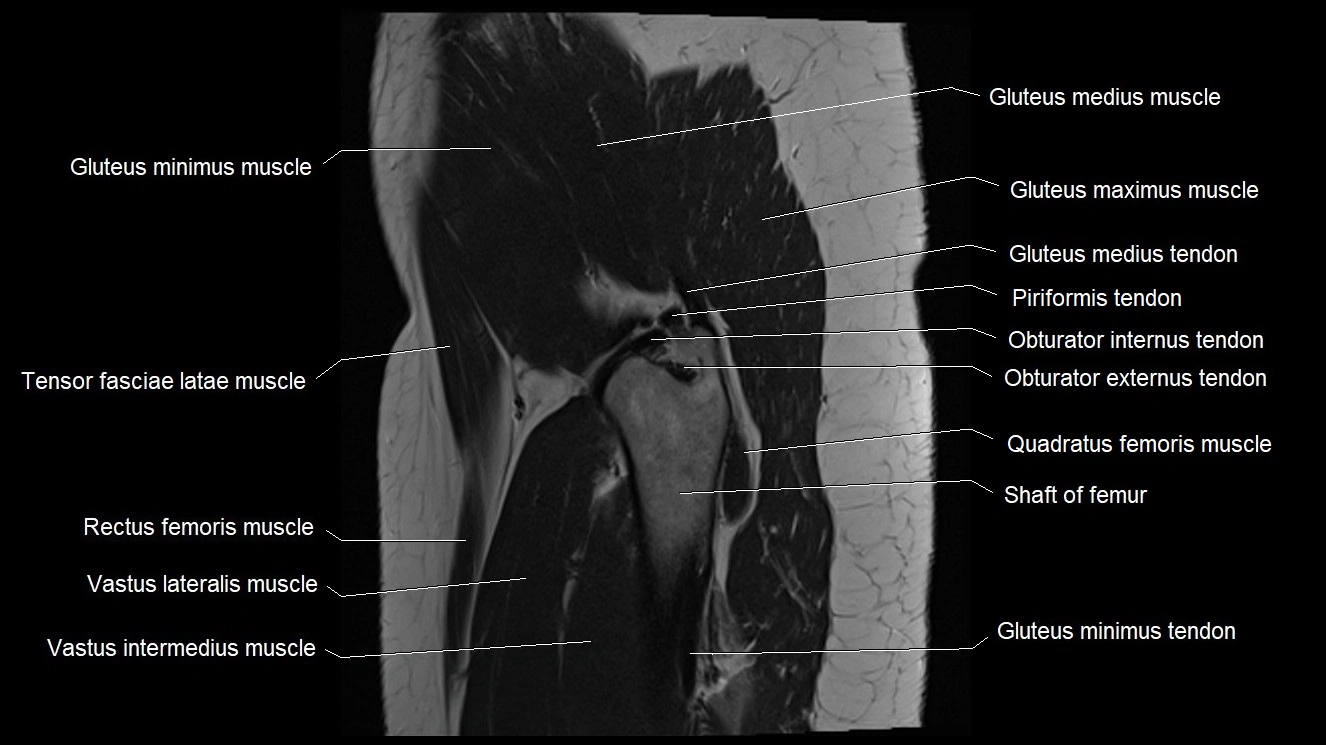

- Gluteus maximus muscle

- Gluteus medius muscle

- Gluteus medius tendon

- Gluteus minimus muscle

- Gluteus minimus tendon

- Greater trochanter

- Obturator externus tendon

- Obturator internus tendon

- Quadratus femoris muscle

- Rectus femoris muscle

- Tensor fasciae latae muscle

- Vastus intermedius muscle

- Vastus lateralis muscle